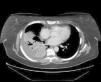

Observación clínicaCaso 1Mujer de 49 años, diagnosticada de artritis reumatoide (AR) a los 40, en tratamiento con metotrexato y esteroides a dosis bajas y, desde febrero de 2006, con adalimumab por vía subcutánea (40mg cada 2 semanas). La AR se hallaba en remisión. Presentaba una prueba de la tuberculina y un efecto de refuerzo negativos. Se había incrementado la dosis de esteroides a 10mg de prednisona ante la presencia de un cuadro indicativo de eritema nudoso 3 meses antes. Acudió a urgencias por cuadro de tos, sudoración profusa y fiebre, que alcanzó 38°C, de 4 semanas de evolución. Se estableció el diagnóstico de neumonía de la comunidad y recibió tratamiento con amoxicilina-ácido clavulánico, sin mejoría, por lo que acudió de nuevo a urgencias. En la radiografía de tórax se apreció una consolidación en el lóbulo inferior derecho. La tomografía computarizada (TAC) mostró una consolidación parenquimatosa en dicho lóbulo (fig. 1). Se inició tratamiento con levofloxacino, con parcial mejoría clínica y radiológica. Al séptimo día reapareció la fiebre. Mediante la inducción de esputo se obtuvo una muestra donde se detectaron bacilos ácido-alcohol resistentes y en la que el cultivo para Mycobacterium tuberculosis complex fue positivo. Se instauró tratamiento con isoniacida, rifampicina y piracinamida. La paciente reingresó al cabo de una semana por vómitos, dolor abdominal e ictericia; la bioquímica hepática mostró bilirrubina de 7,3U/l, a expensas de bilirrubina directa; aspartato aminotransferasa de 146U/l, alanina aminotransferasa de 158U/l, fosfatasa alcalina de 515U/l y gammaglutamil transpeptidasa de 136U/l. Se interrumpió el tratamiento tuberculostático. A los 11 días del ingreso se reinstauraron progresivamente la isoniacida y la rifampicina, y se inició estreptomicina, hasta que las pruebas de sensibilidad permitieron retirarla. La evolución posterior de la paciente fue buena y su AR está en remisión.